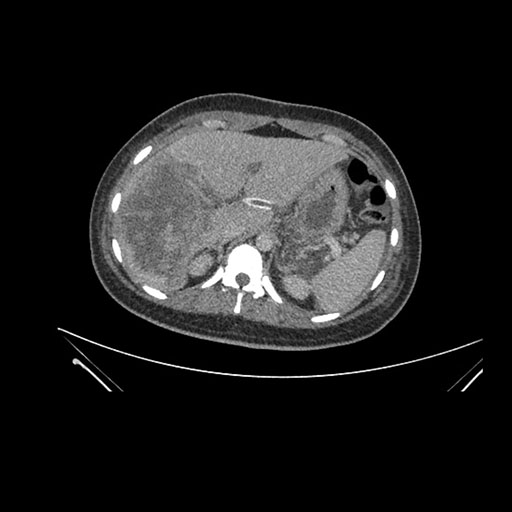

Axial Venous